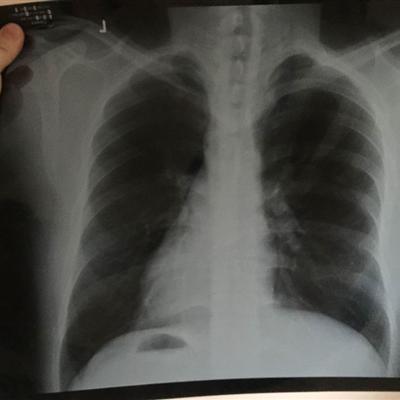

First, if the cough is too severe, it can cause lung pain. If it is confirmed that it is caused by cough, we must go to the hospital for treatment in time. The causes of these situations are due to the lack of systemic and local immune function of the patients, the imperfect development of respiratory tract and lung, and the recurrent cough.

Second: infants are prone to bronchiolitis, a form of pneumonia. Children with bad face, often purple, or breathing faster, shoulder breathing, and inhaled chest wall depression, should also be sent to the hospital in time.